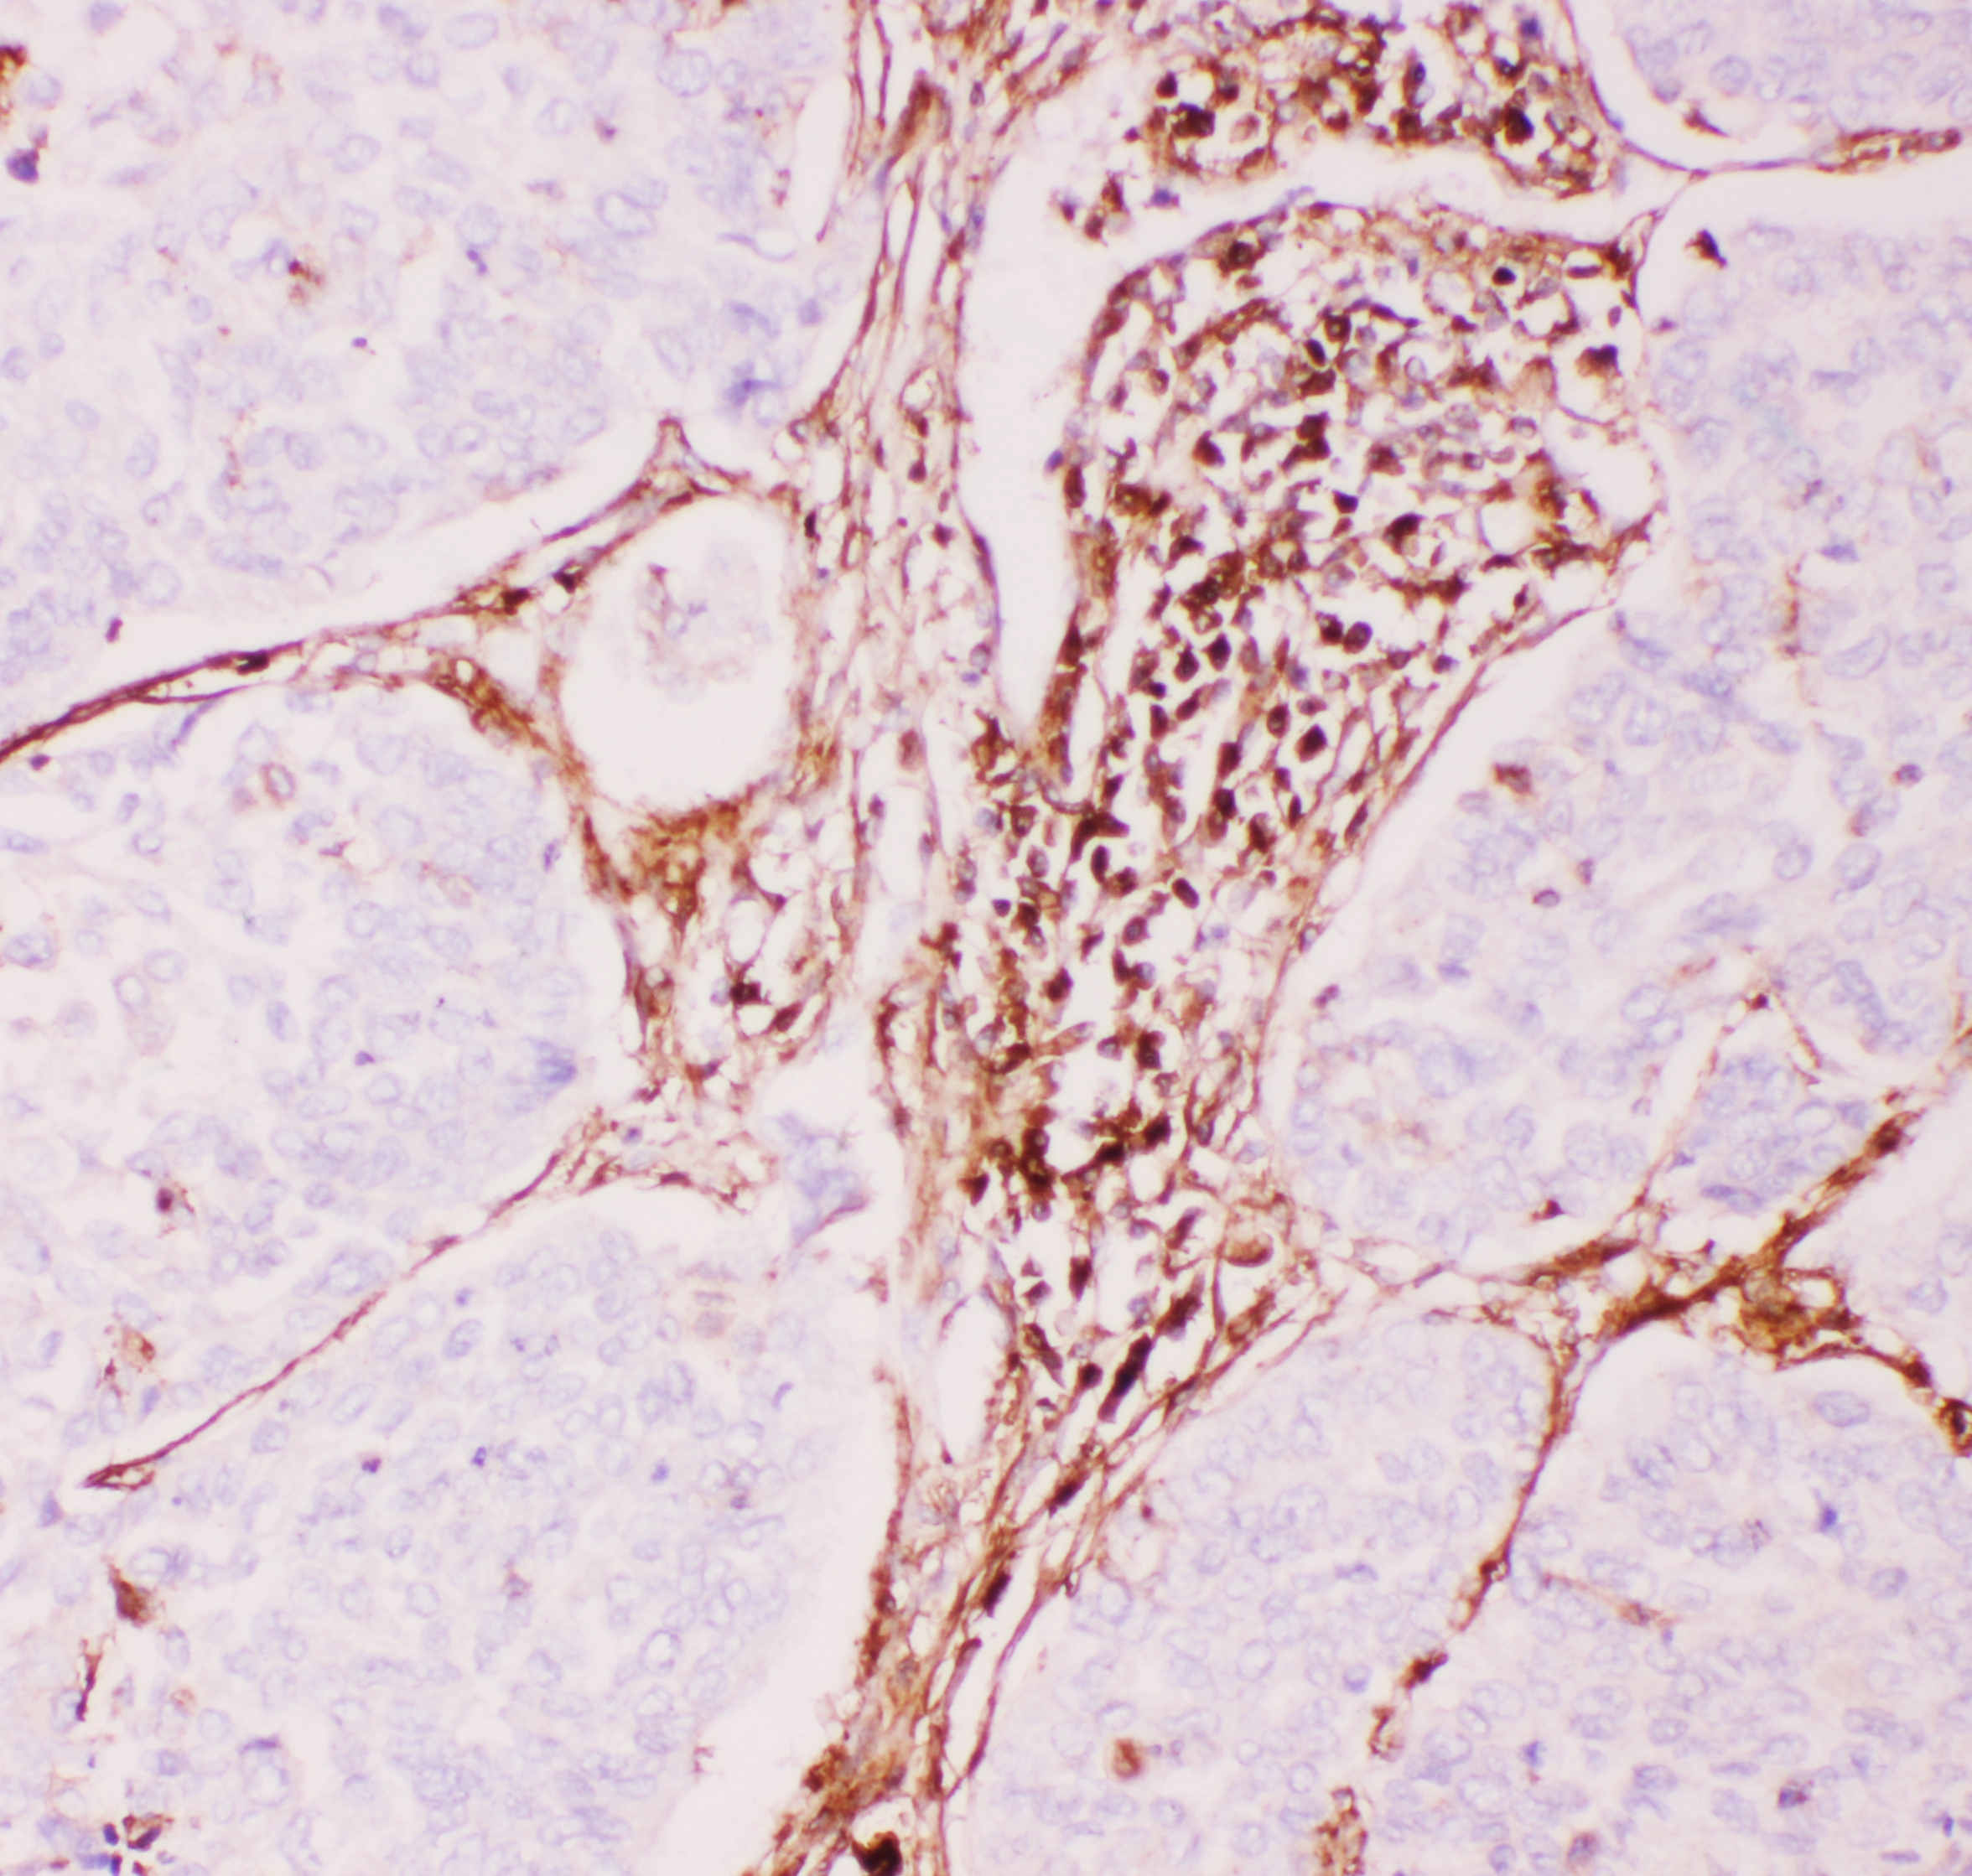

IHC analysis of P glycoprotein/ABCB1 using anti-P glycoprotein/ABCB1 antibody (PB0162).

P glycoprotein/ABCB1 was detected in a paraffin-embedded section of human lung cancer tissue. The tissue section was incubated with rabbit anti-P glycoprotein/ABCB1 Antibody (PB0162) at a dilution of 1:200 and developed using HRP Conjugated Rabbit IgG Super Vision Assay Kit (Catalog # SV0002) with DAB (Catalog # AR1027) as the chromogen.